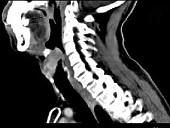

问题 男,53岁,咽部不适半年余,近两个月感咽部疼痛,声嘶,CT如图所示,应诊断为()

选项 A.乳头状瘤 B.喉癌 C.梨状窝癌 D.喉肉芽肿 E.喉部纤维瘤

答案 B